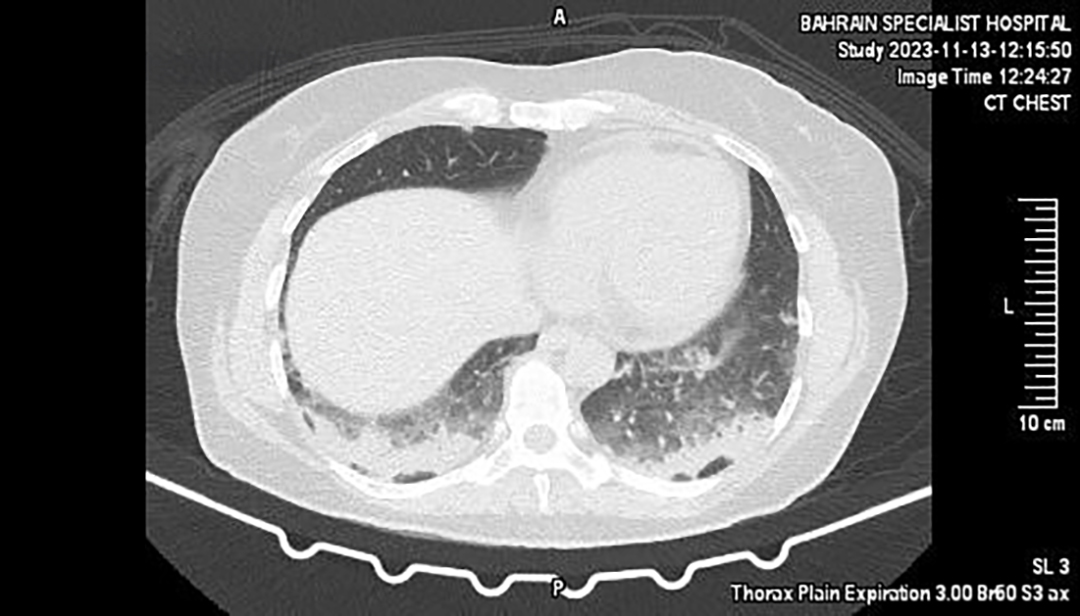

Initial investigations — including routine blood tests — returned mostly normal, save for an elevated C-reactive protein (CRP), hinting at underlying inflammation. Imaging studies via chest radiograph and high-resolution CT (HRCT) revealed bilateral subpleural and patchy consolidations, raising concerns about a non-resolving pulmonary condition.